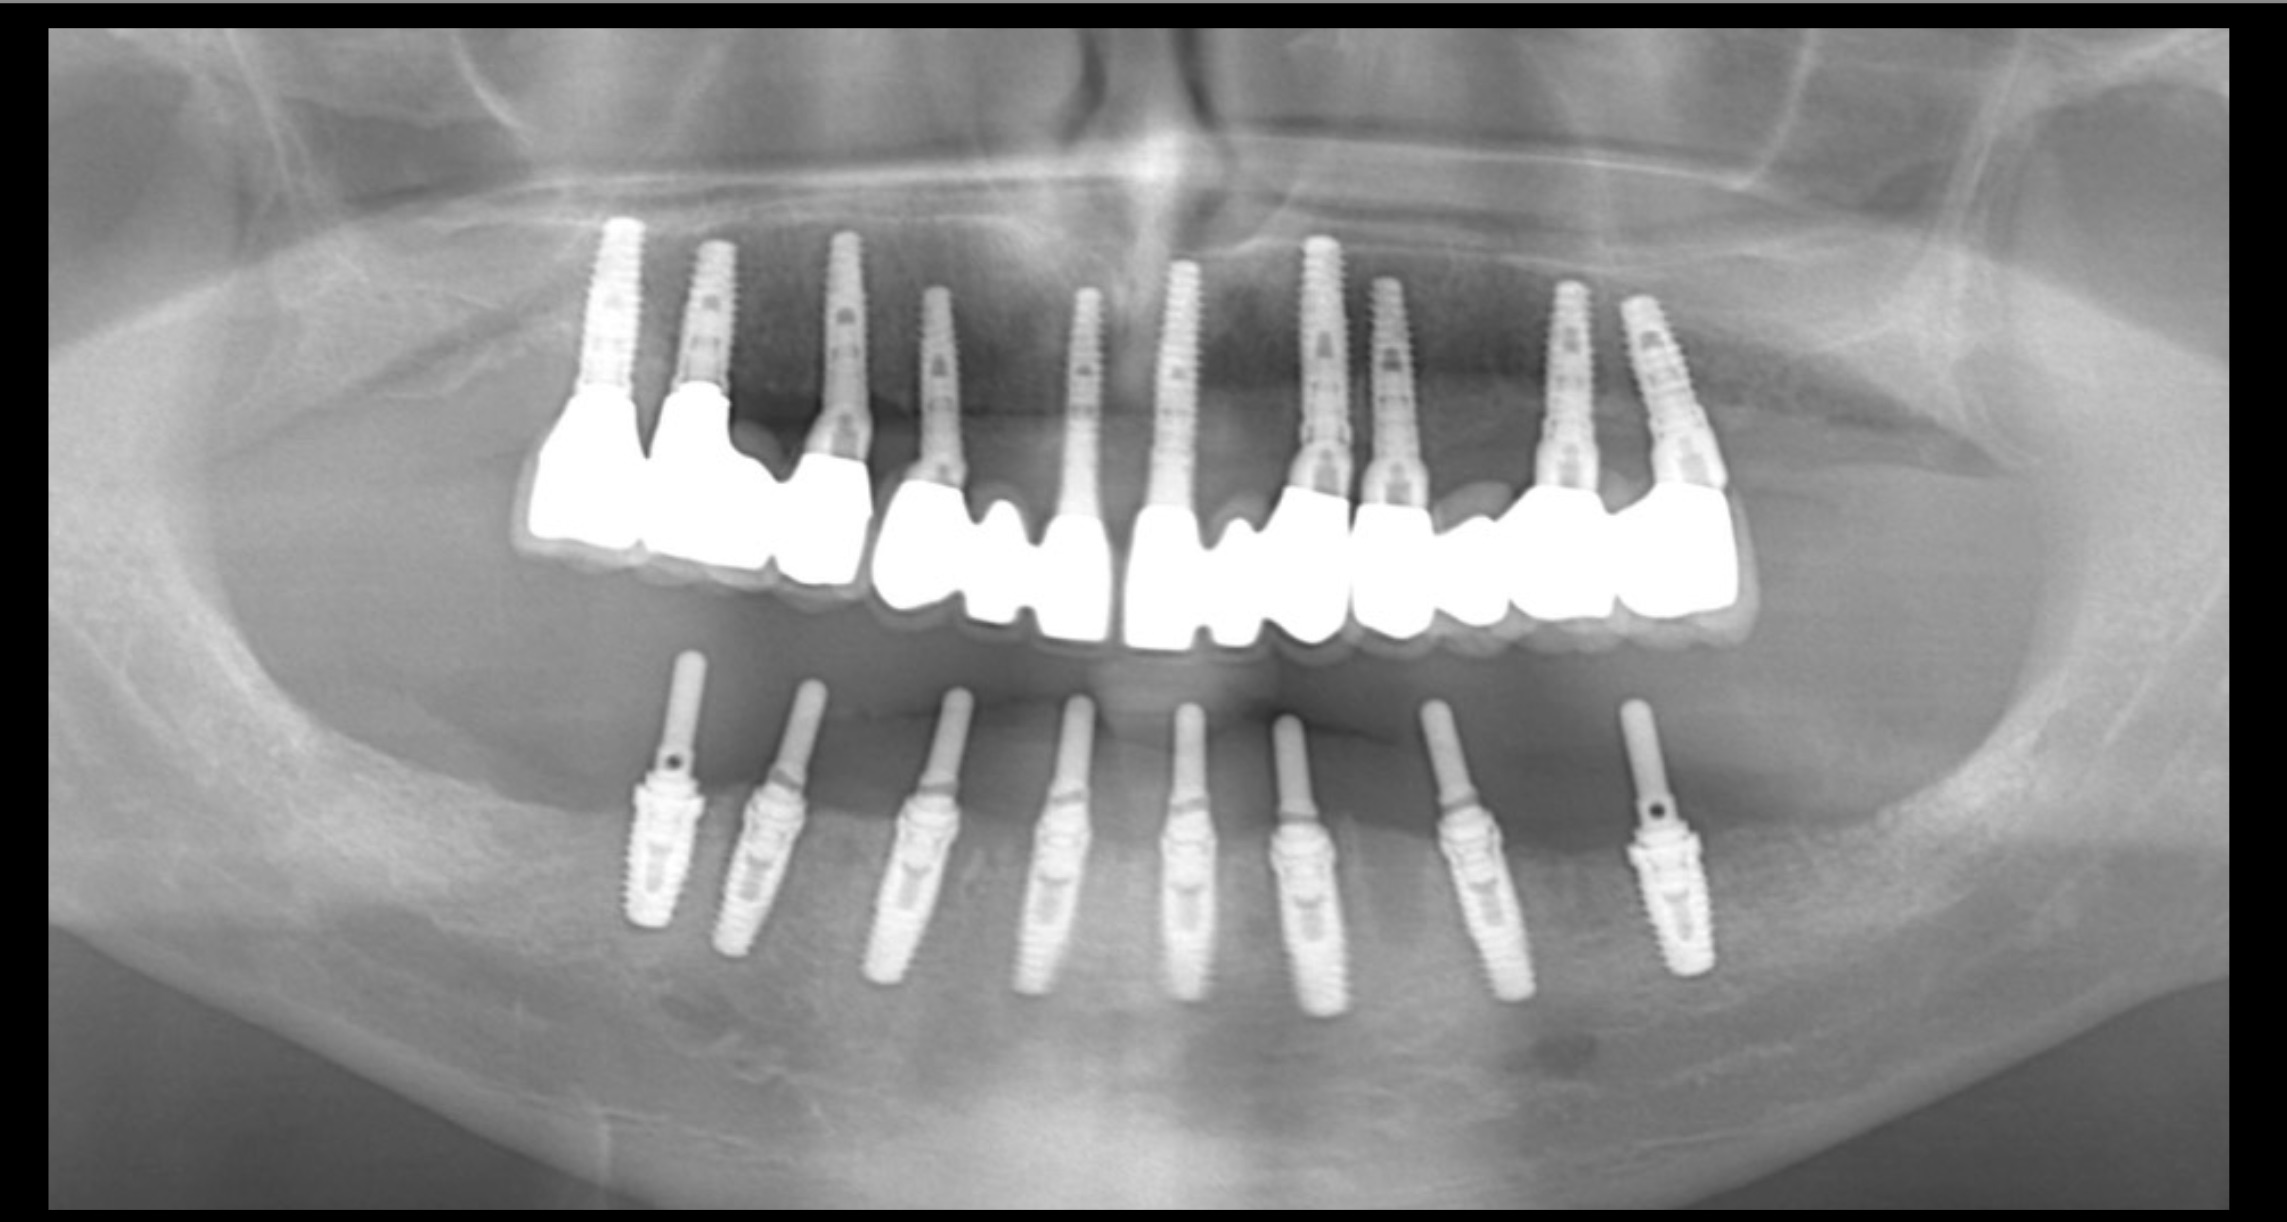

שתלים הינם עקרונית ברגי טיטאניום המוברגים לעצם הלסת ומהווים תחליף לשרש שן חסרה. ועליהם ניתן להבריג כתר בודד, או גשרים בין כמה שתלים שהם שחזור של השיניים שהלכו לאיבוד עקב עקירה מסיבות שונות. במקרה של חוסר שיניים אחוריות הם הפתרון היחיד לתותב קבוע - גשר כתחליף לשיניים חסרות. על שתלים ניתן גם להתאים ״תותבות על״ לשיפור אחיזת תותבת (בעיקר תותבת תחתונה)